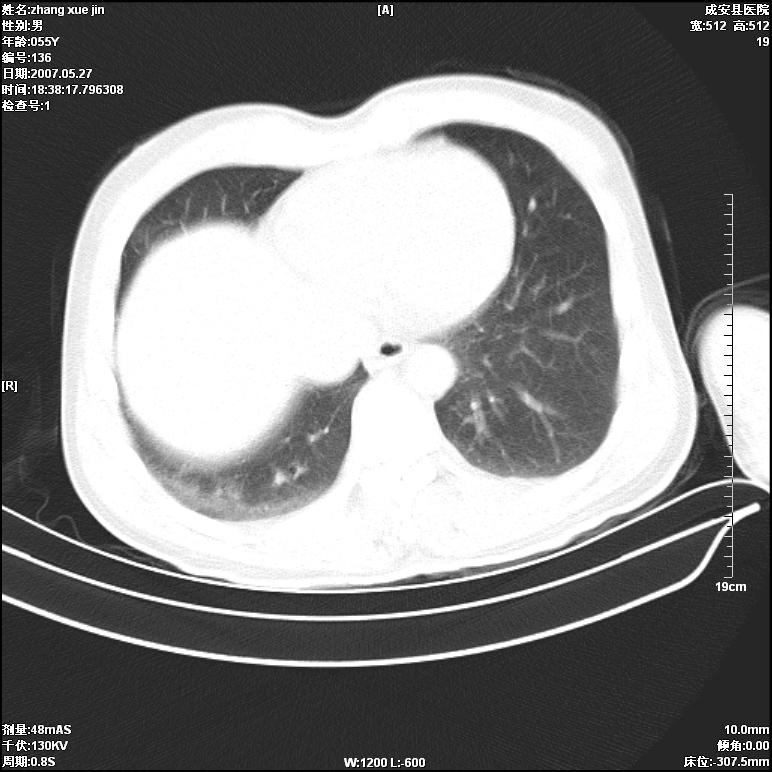

病人 男 53岁 从高处摔伤 行胸部ct检查,纵隔窗没事未上传,肺窗示,右侧胸膜下见条状稍高密度影,是胸膜下线还是右下肺轻度挫伤?意见不一,请分析。

右肺下叶胸膜下弧形窄带状模糊影,结合病史,考虑肺挫伤。

支持肺挫伤,如果48小时阴影继续扩大,应疑有继发感染

体位不正,左侧纵隔旁胸膜下亦见条带状略高密度影,考虑为坠积效应所致。

气管内见一小液平面,